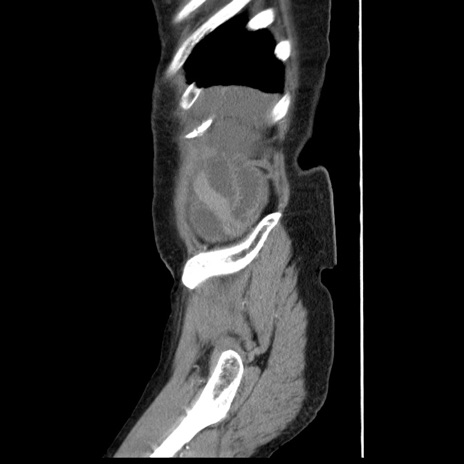

症例1(矢状断像)

【症例】80歳代女性

【主訴】腹痛

【現病歴】8時間前から腹痛あり来院。

【既往歴】糖尿病、脂質異常症、子宮体癌にて子宮全摘術

【身体所見】意識清明・会話良好だが腹痛で苦悶様、全腹部にわたって反跳痛と圧痛あり

【データ】WBC 13600、CRP 0.14、LDH 224、CK 90